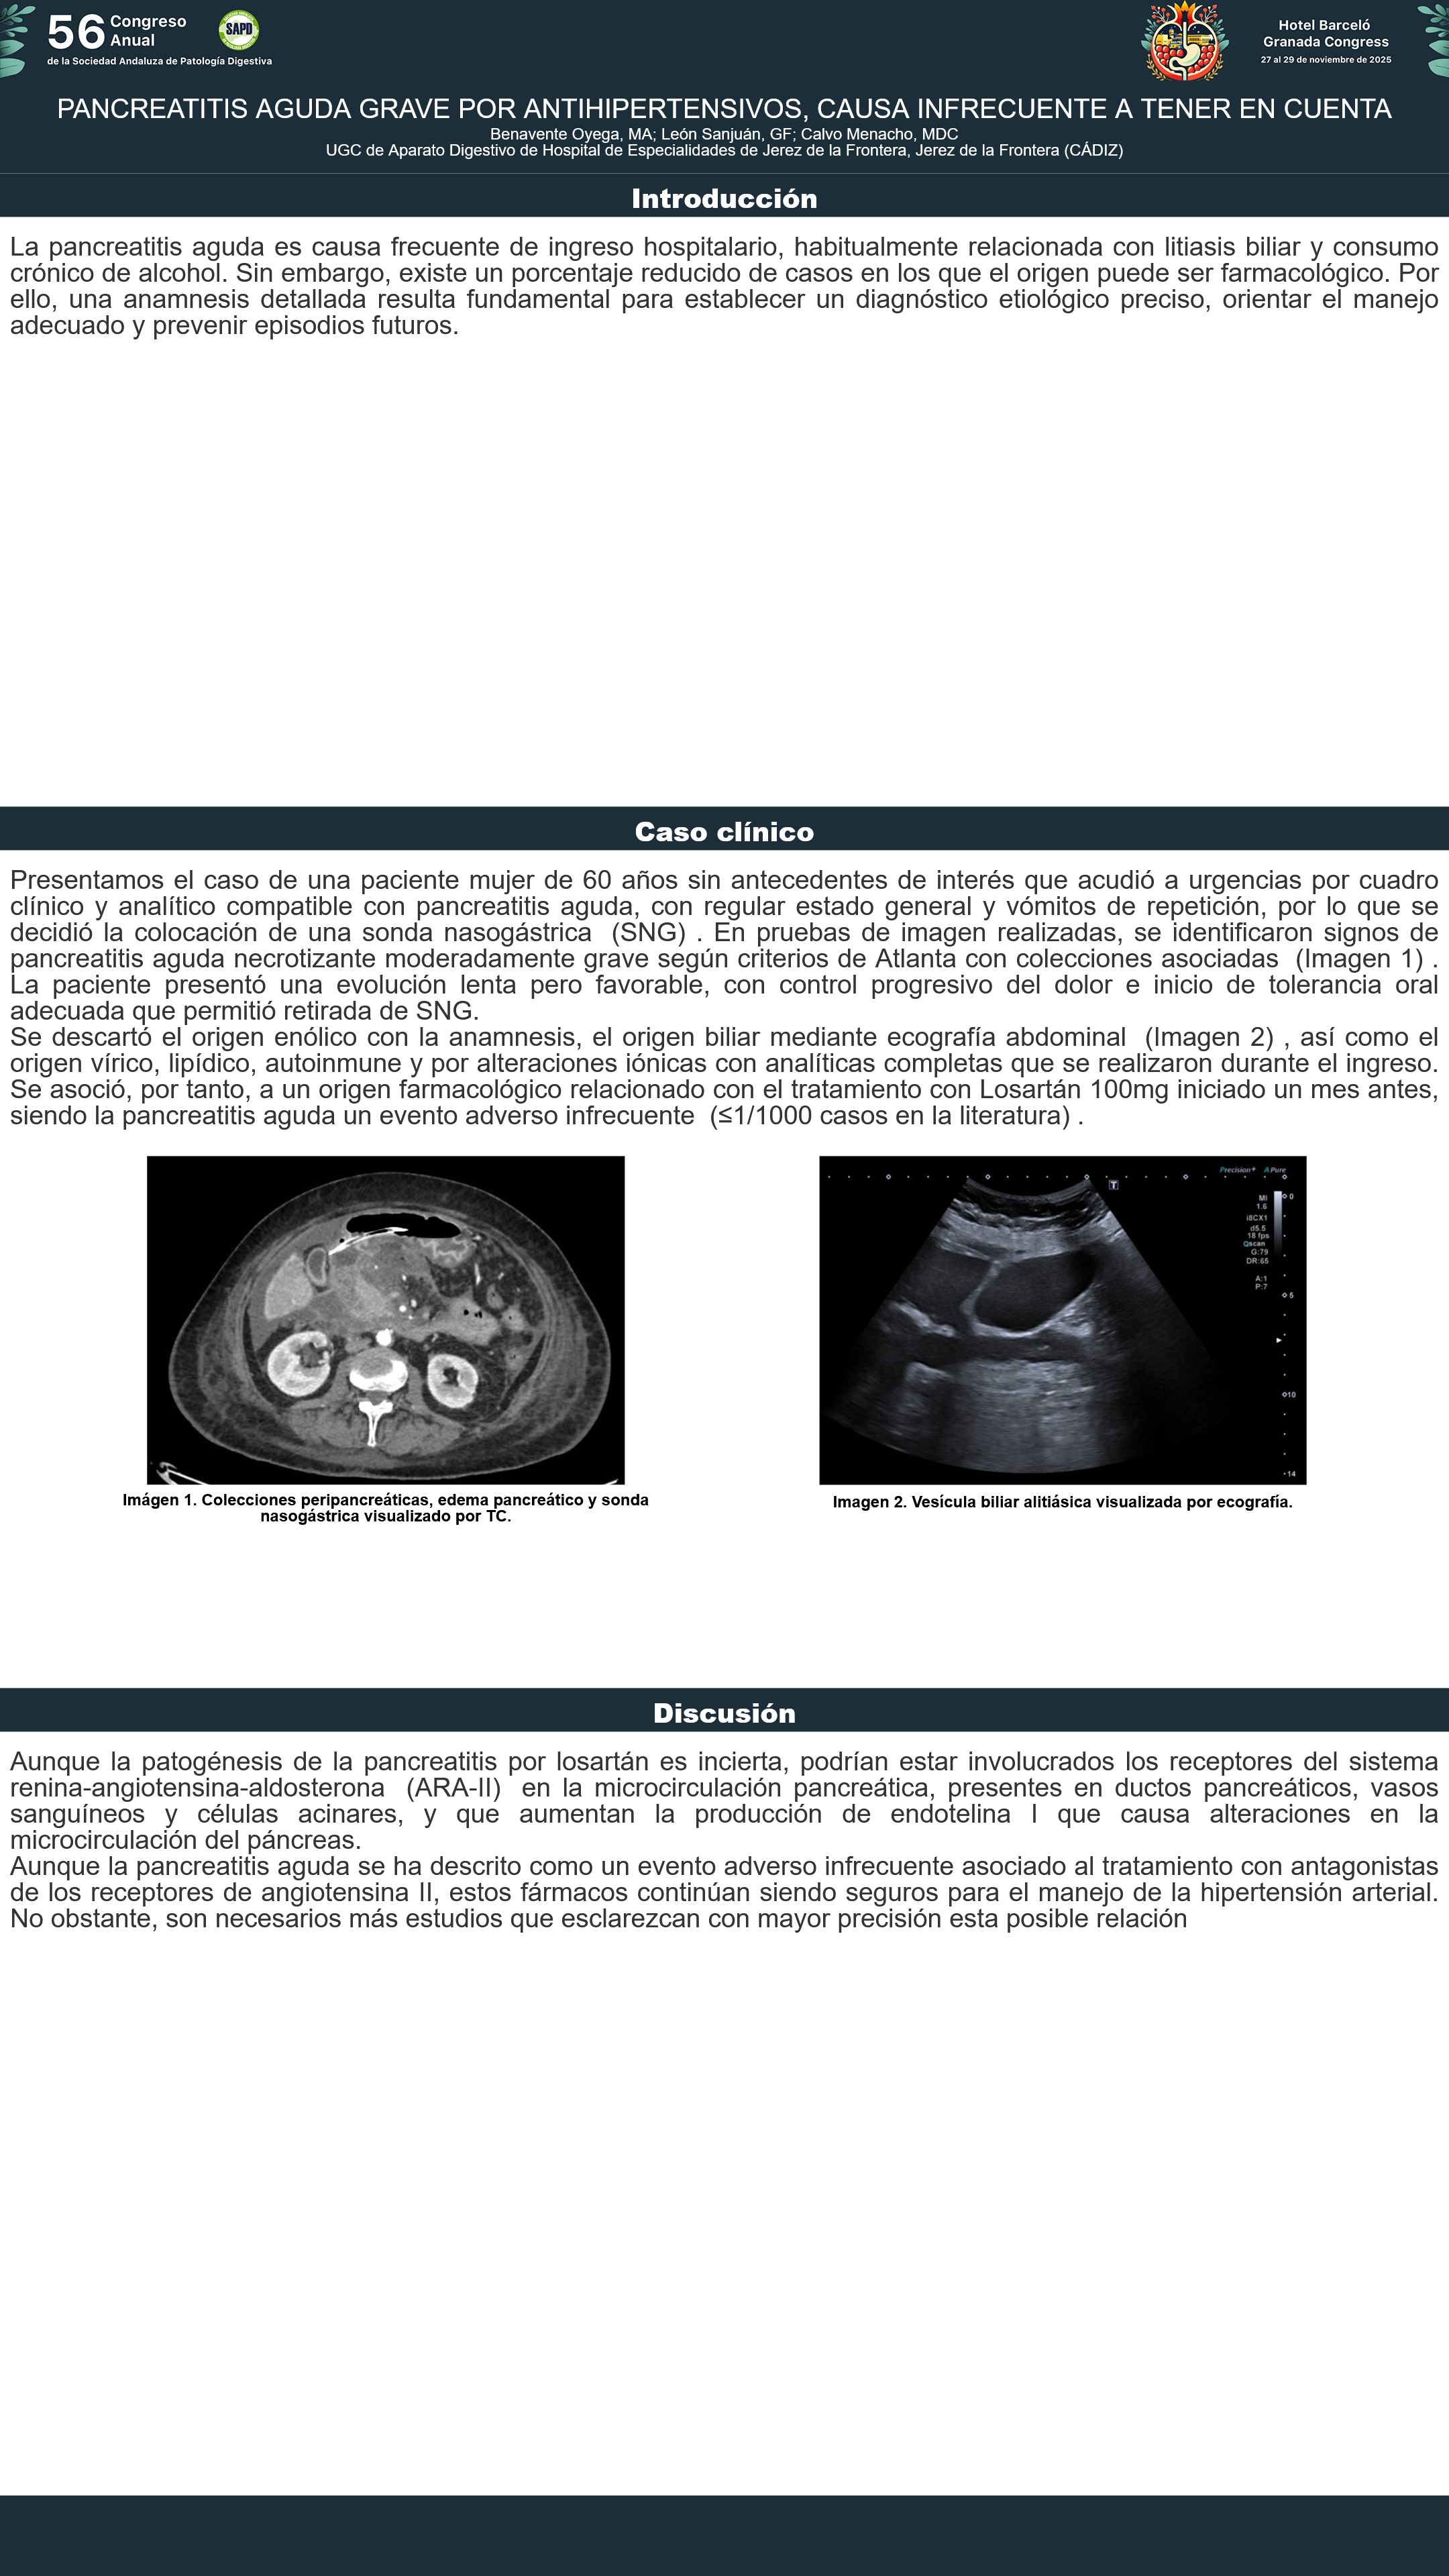

[CP-146] PANCREATITIS AGUDA GRAVE POR ANTIHIPERTENSIVOS, CAUSA INFRECUENTE A TENER EN CUENTA